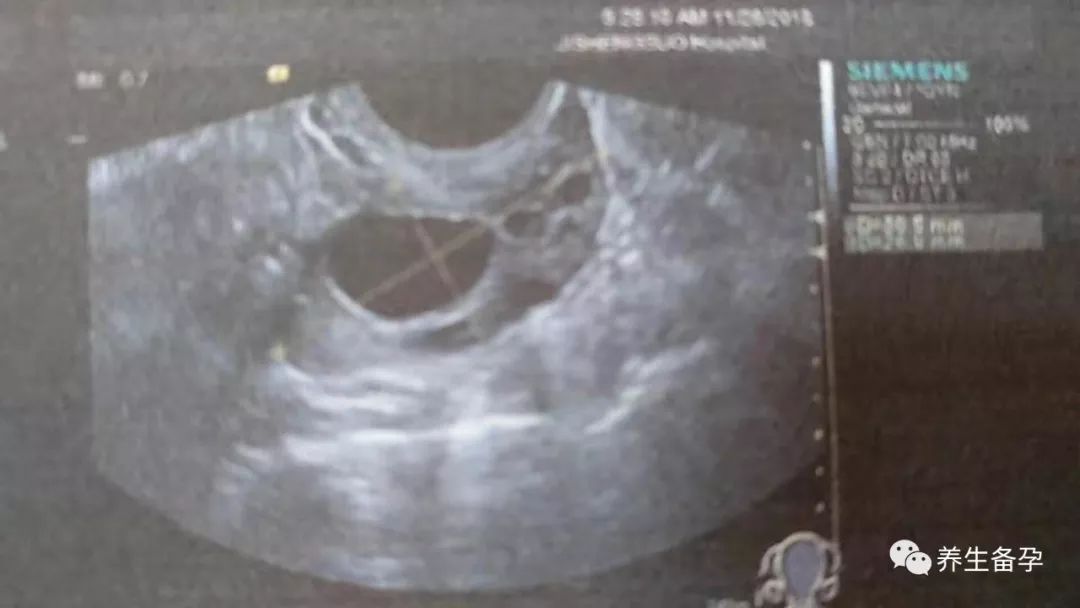

下面给大家看看卵泡质量比较好的照片。